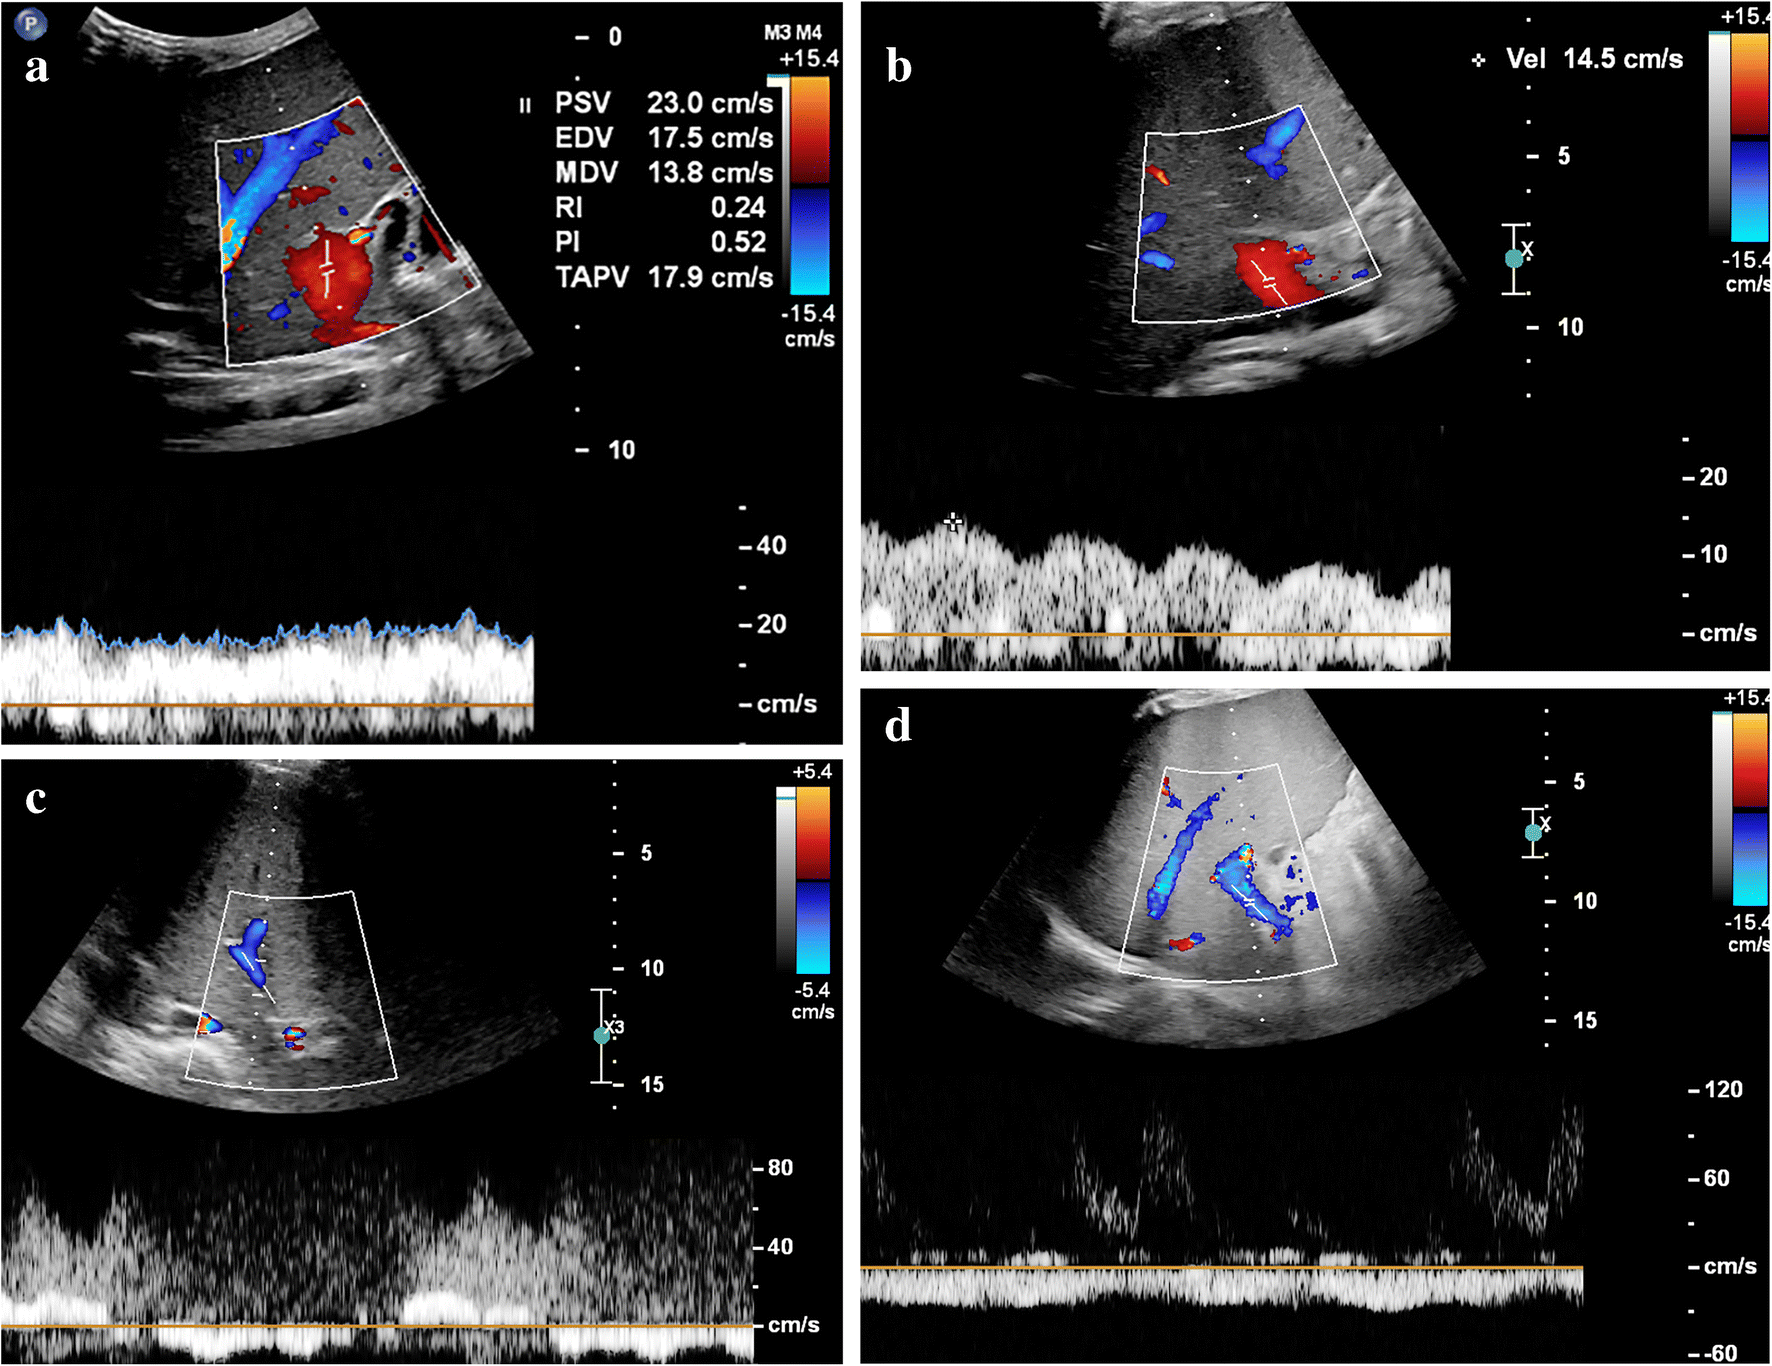

Fig. 1

Different hepatic portal vein flow patterns can be observed in sinusoidal obstruction syndrome. a An axial intercostal transverse color Doppler ultrasound (US) image of the liver shows normal hepatic portal flow direction, velocity and pattern in a 10-month-old boy with juvenile myelomonocytic leukemia who developed severe sinusoidal obstruction syndrome 7 days after allogeneic stem cell transplantation. This was the initial US examination; hepatomegaly and ascites confirmed the clinical suspicion of sinusoidal obstruction syndrome. b An axial intercostal transverse color Doppler US image of the liver in a 4-year old girl with severe sinusoidal obstruction syndrome 21 days after autologous stem cell transplantation, and 5 days after the first clinical suspicion based on elevation of liver transaminases. Increased pulsatility of the portal vein flow pattern with decreased velocities of 10–15 cm/s. c An axial intercostal transverse color Doppler US image of the liver in a 14-year-old girl with neuroblastoma and severe sinusoidal obstruction syndrome shows a to-and-fro flow pattern 5 weeks after autologous stem cell transplantation and 1 week after the first clinical suspicion of the disease. d An axial intercostal transverse color Doppler US image of the liver in a 4-year-old boy with severe sinusoidal obstruction syndrome 29 days after autologous stem cell transplantation shows hepatofugal flow direction in the portal vein. Abnormal portal vein flow patterns resolved on follow-up, in keeping with the clinical resolution of sinusoidal obstruction syndrome